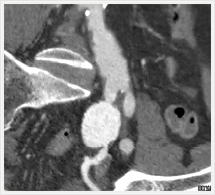

CT検査

当院は64列・320列と2台のマルチスライスCTで運用されており、診断目的に合わせた撮影条件で迅速かつ安全で質の高い画像提供を行っております。

- 得られる画像は輪切り(冠状断)像です。

- わずかなX線の吸収差を画像にすることができます。

- 脳内の出血などの場合、その漏出した血液の範囲を明瞭に識別できます。

- 造影検査では、ヨード造影剤を併用することにより血管の走行など、より多くの情報をもった画像を得ることができます。

- 撮影されたCT画像をされにコンピュータで処理することにより、体軸に対する自由な輪切りの断面画像を作ることができます。

画像紹介

CTでは輪切り像の他にも立体的な画像(3D画像)を作成することもできます。そのためにはより細かくキレイな画像を撮影しなければなりません。当院では64列CTを導入しており、キレイな画像をより細かく撮影することができます。その画像を元に3D画像を作成することによって、より正確な手術のシミュレーションが可能になります。実際に手術をしたときの様子が、手術をする前に画像として見らます。外科系の手術には欠かせない技術となっておりますが、内科系でも血管内手術にも多く利用されております。